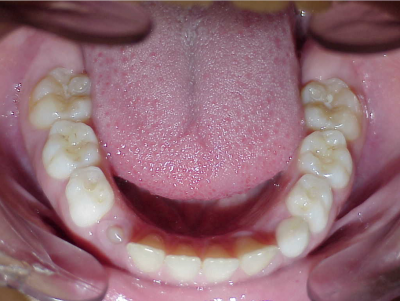

eindfoto